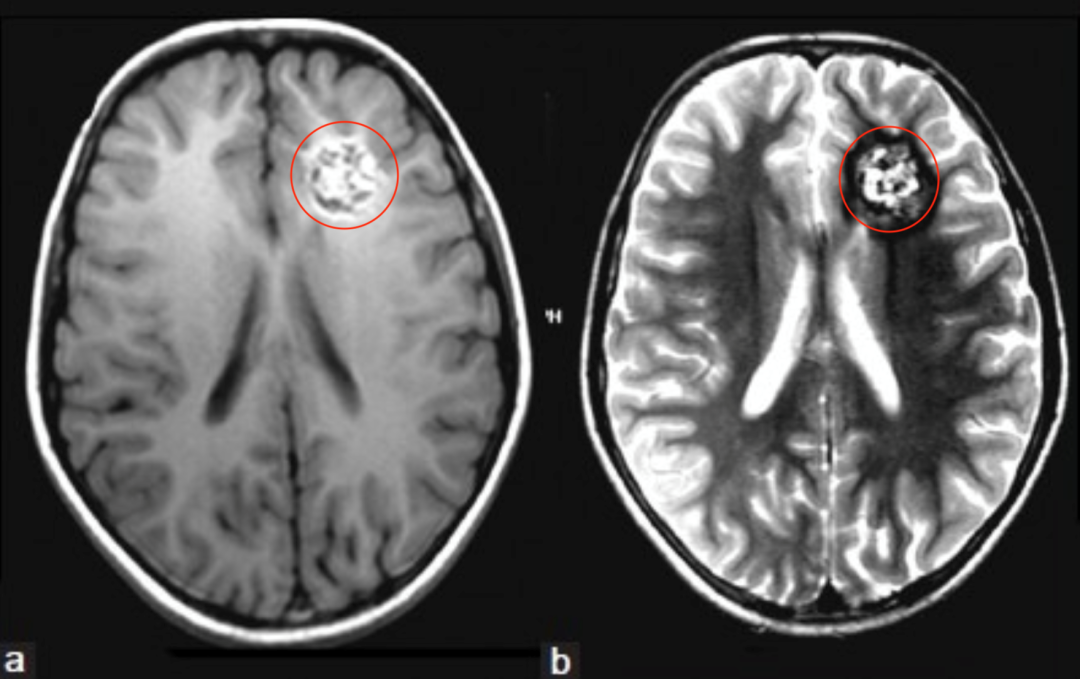

影像学检查显示:矢状位CISS序列可见导水管入口明显狭窄,IRTSE序列显示导水管内脑脊液流动正常,术前T2加权像显示侧脑室宽度正...